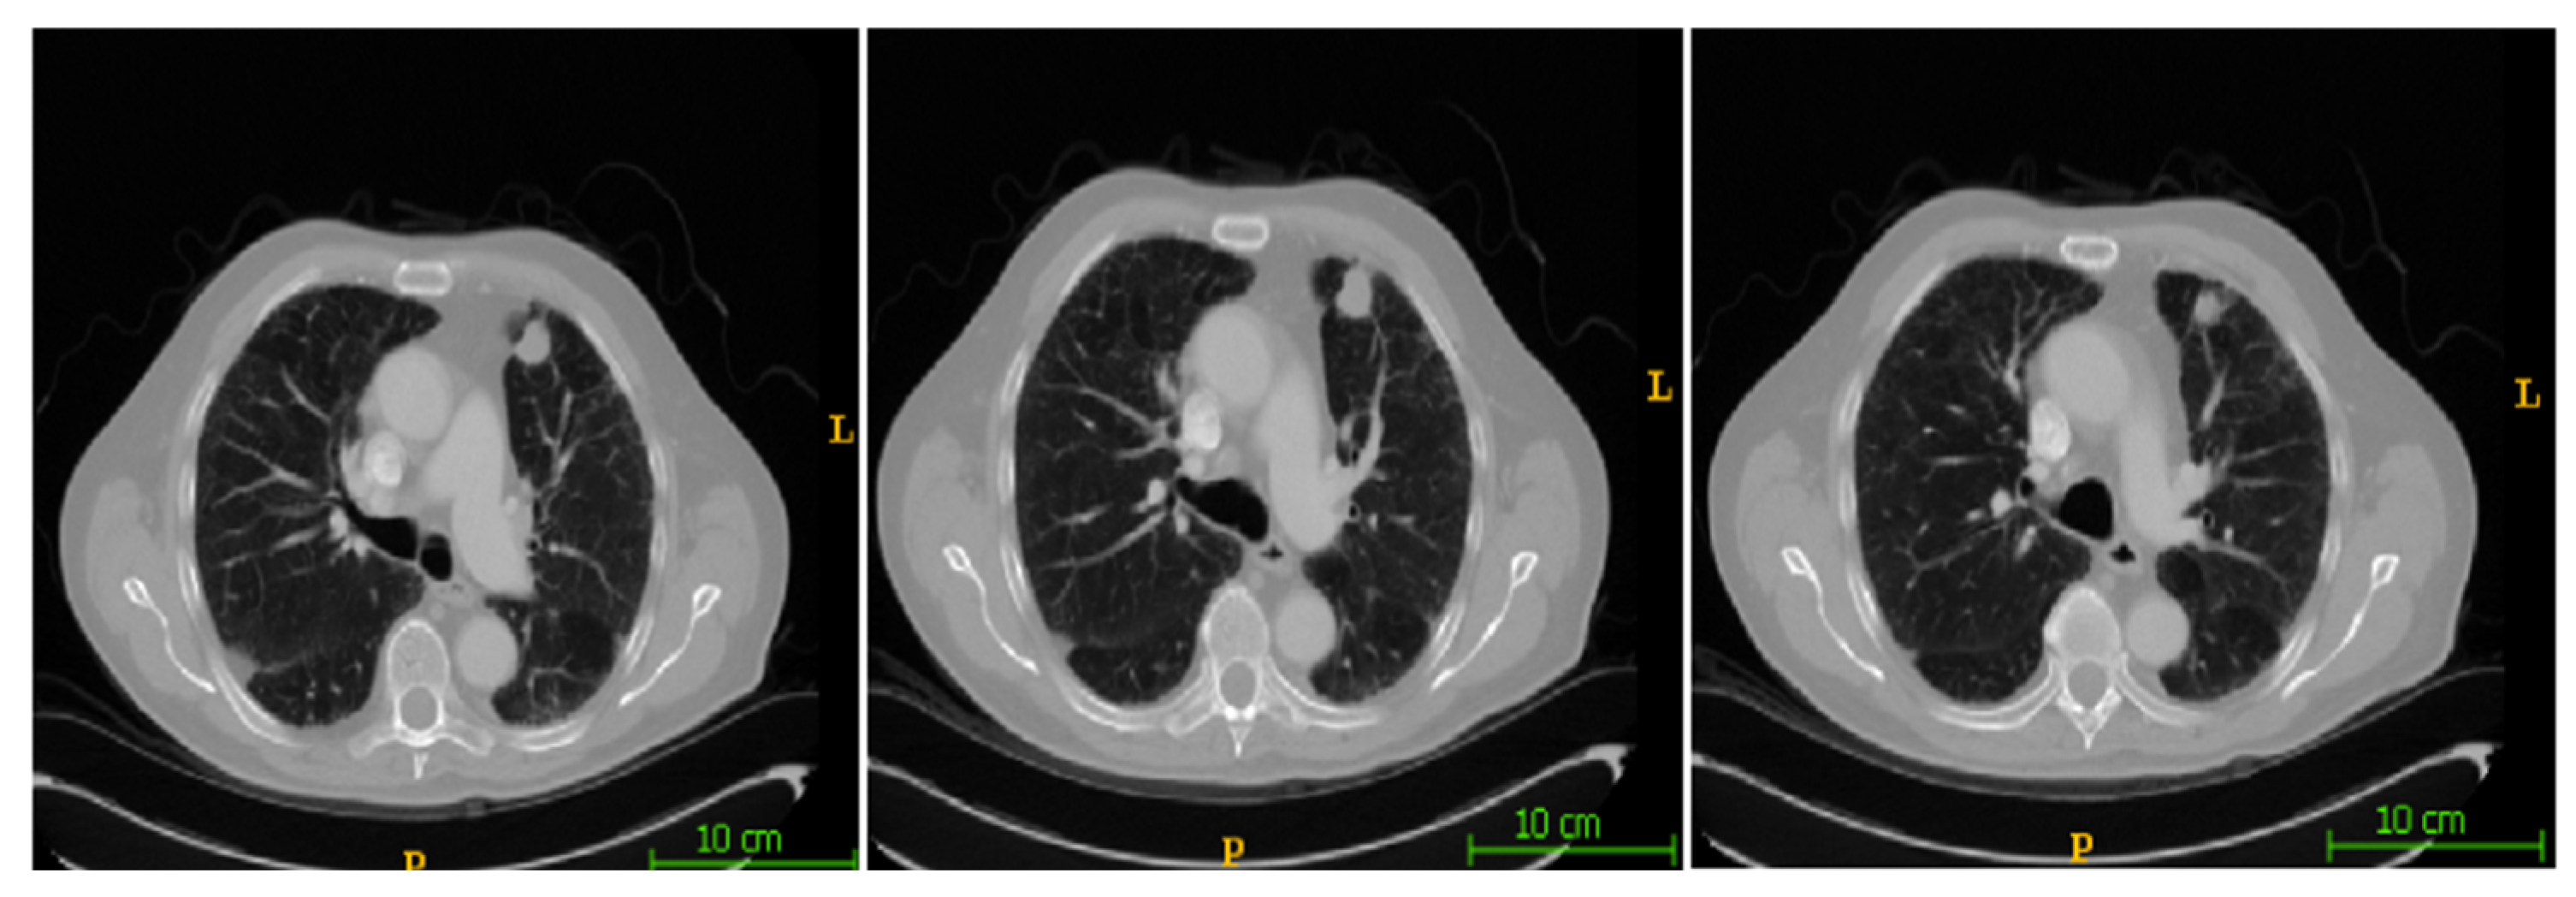

In this section, the segmentation results of the RW-ensemble are visualized for distinct types of nodules. The results for three different types of nodules from the LCT-D dataset are demonstrated: solid nodules, juxta-vascular, and pleural nodules. To improve clarity, each case is visualized through CT slices and the corresponding RW-ensemble segmented outputs, organized by nodule type and patient ID. Figure 6 and Figure 7 represent the solid nodule and its respective RW-E segmented images in grey-scale for patient R_0108. The juxta-vascular nodules of patient R_0052 are shown in Figure 8, and the corresponding RW-E segmented output images are illustrated in Figure 9. Juxta-pleural nodules, which are challenging due to their attachment to the lung wall, are illustrated in Figure 10 and Figure 11 for patient QIN_LSC_0064.

Figure 11. RW-ensemble segmentation output of juxta-pleural nodules in grey-scale.

Bioengineering 12 00576 g011